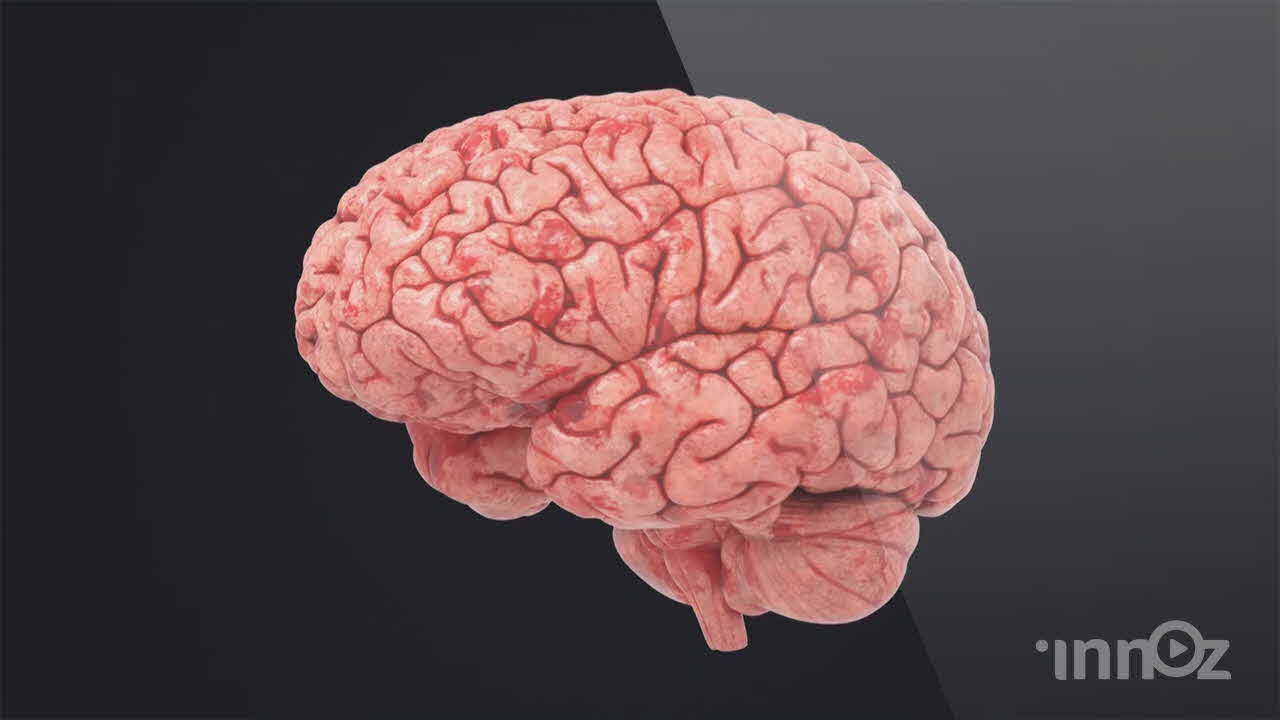

이노즈는 AI영상제작, 3D영상 제작 전문기업으로, 다양한 산업 분야에 걸쳐 혁신적이고 몰입감 있는 3D 콘텐츠를 제공합니다. 제품 홍보, 건설 시뮬레이션, 애니메이션 등 맞춤형 영상으로 고객사의 가치를 시각적으로 효과적으로 전달합니다. 고품질의 3D 시각화와 창의적인 연출을 바탕으로, 고객의 목표를 실현하는 독창적이고 강력한 시각적 경험을 제공합니다. 이노즈의 포트폴리오는 고객의 아이디어를 현실로 구현한 다양한 성공적인 프로젝트로 가득합니다.

2021 아리바이오 뇌 세포 영상제작

아리바이오